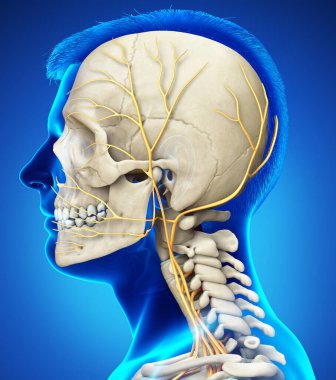

iskelet adam yan görünüm baş ve sinir sistemi

Geniş Lisanslama

(5000 x 5000, jpg)